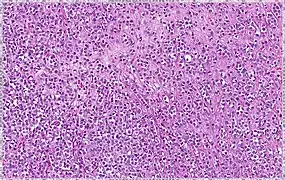

| Classical | 40% | Round or ovoid cells with little cytoplasm in a single-file infiltrating pattern, sometimes concentrically giving a targetoid pattern | ![]() |

| Pleomorphic | Classical-appearing but with pleomorphic cells. It may include signet-ring cells, or plasmacytoid cells (pictured) which have abundant cytoplasm and eccentric nuclei. | ![]() |

Histopathology of invasive lobular carcinoma (ILC), next to lobular carcinoma in situ (LCIS).

Invasive lobular carcinoma demonstrating a predominantly lobular growth pattern.

Lobular breast cancer. Single file cells and cell nests.